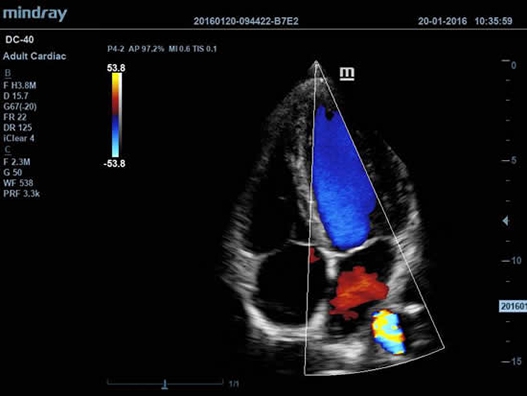

Mindray DC-40 - передовая УЗ-станция с выдающимися возможностями в области медицинской диагностики. Компания Mindray разработала это устройство с учетом высоких требований врачей к качеству изображения и быстродействию. DC-40 обеспечивает высокое качество изображения и точность диагностики, что является необходимым в повседневной практике врачей. Технологии, применяемые в этом устройстве, позволяют получать четкое и детализированное изображение.

DC-40 имеет особое применение в кардиологической практике, благодаря функции Free Xros CM. Она позволяет отслеживать движения сердечной мышцы в различных фазах и одновременно определять синхронизацию миокарда. Это существенно повышает точность диагноза.

• Функции анатомического режима Free Xros M и Free Xros CM позволяют точно расчитывать анатомические параметры и отслеживать движения сердечной мышцы.

• TDI (Tissue Doppler imaging, including TDI Color, Power, PW and M mode) – пакет тканевой допплерографии, включая цветное картирование, импульсный тканевой допплер, энергетический тканевой допплер и тканевой М-режим;

• Free Xros M™ - анатомический М-режим - это возможность вращения курсора в М-режиме под произвольным углом (при фиксированном положении датчика) и, соответственно, получения графика движения структур сердца в различных произвольных плоскостях;

• Free Xros CM™ - огибающий анатомический М-режим;

• Секторный фазированный датчик Mindray P4-2